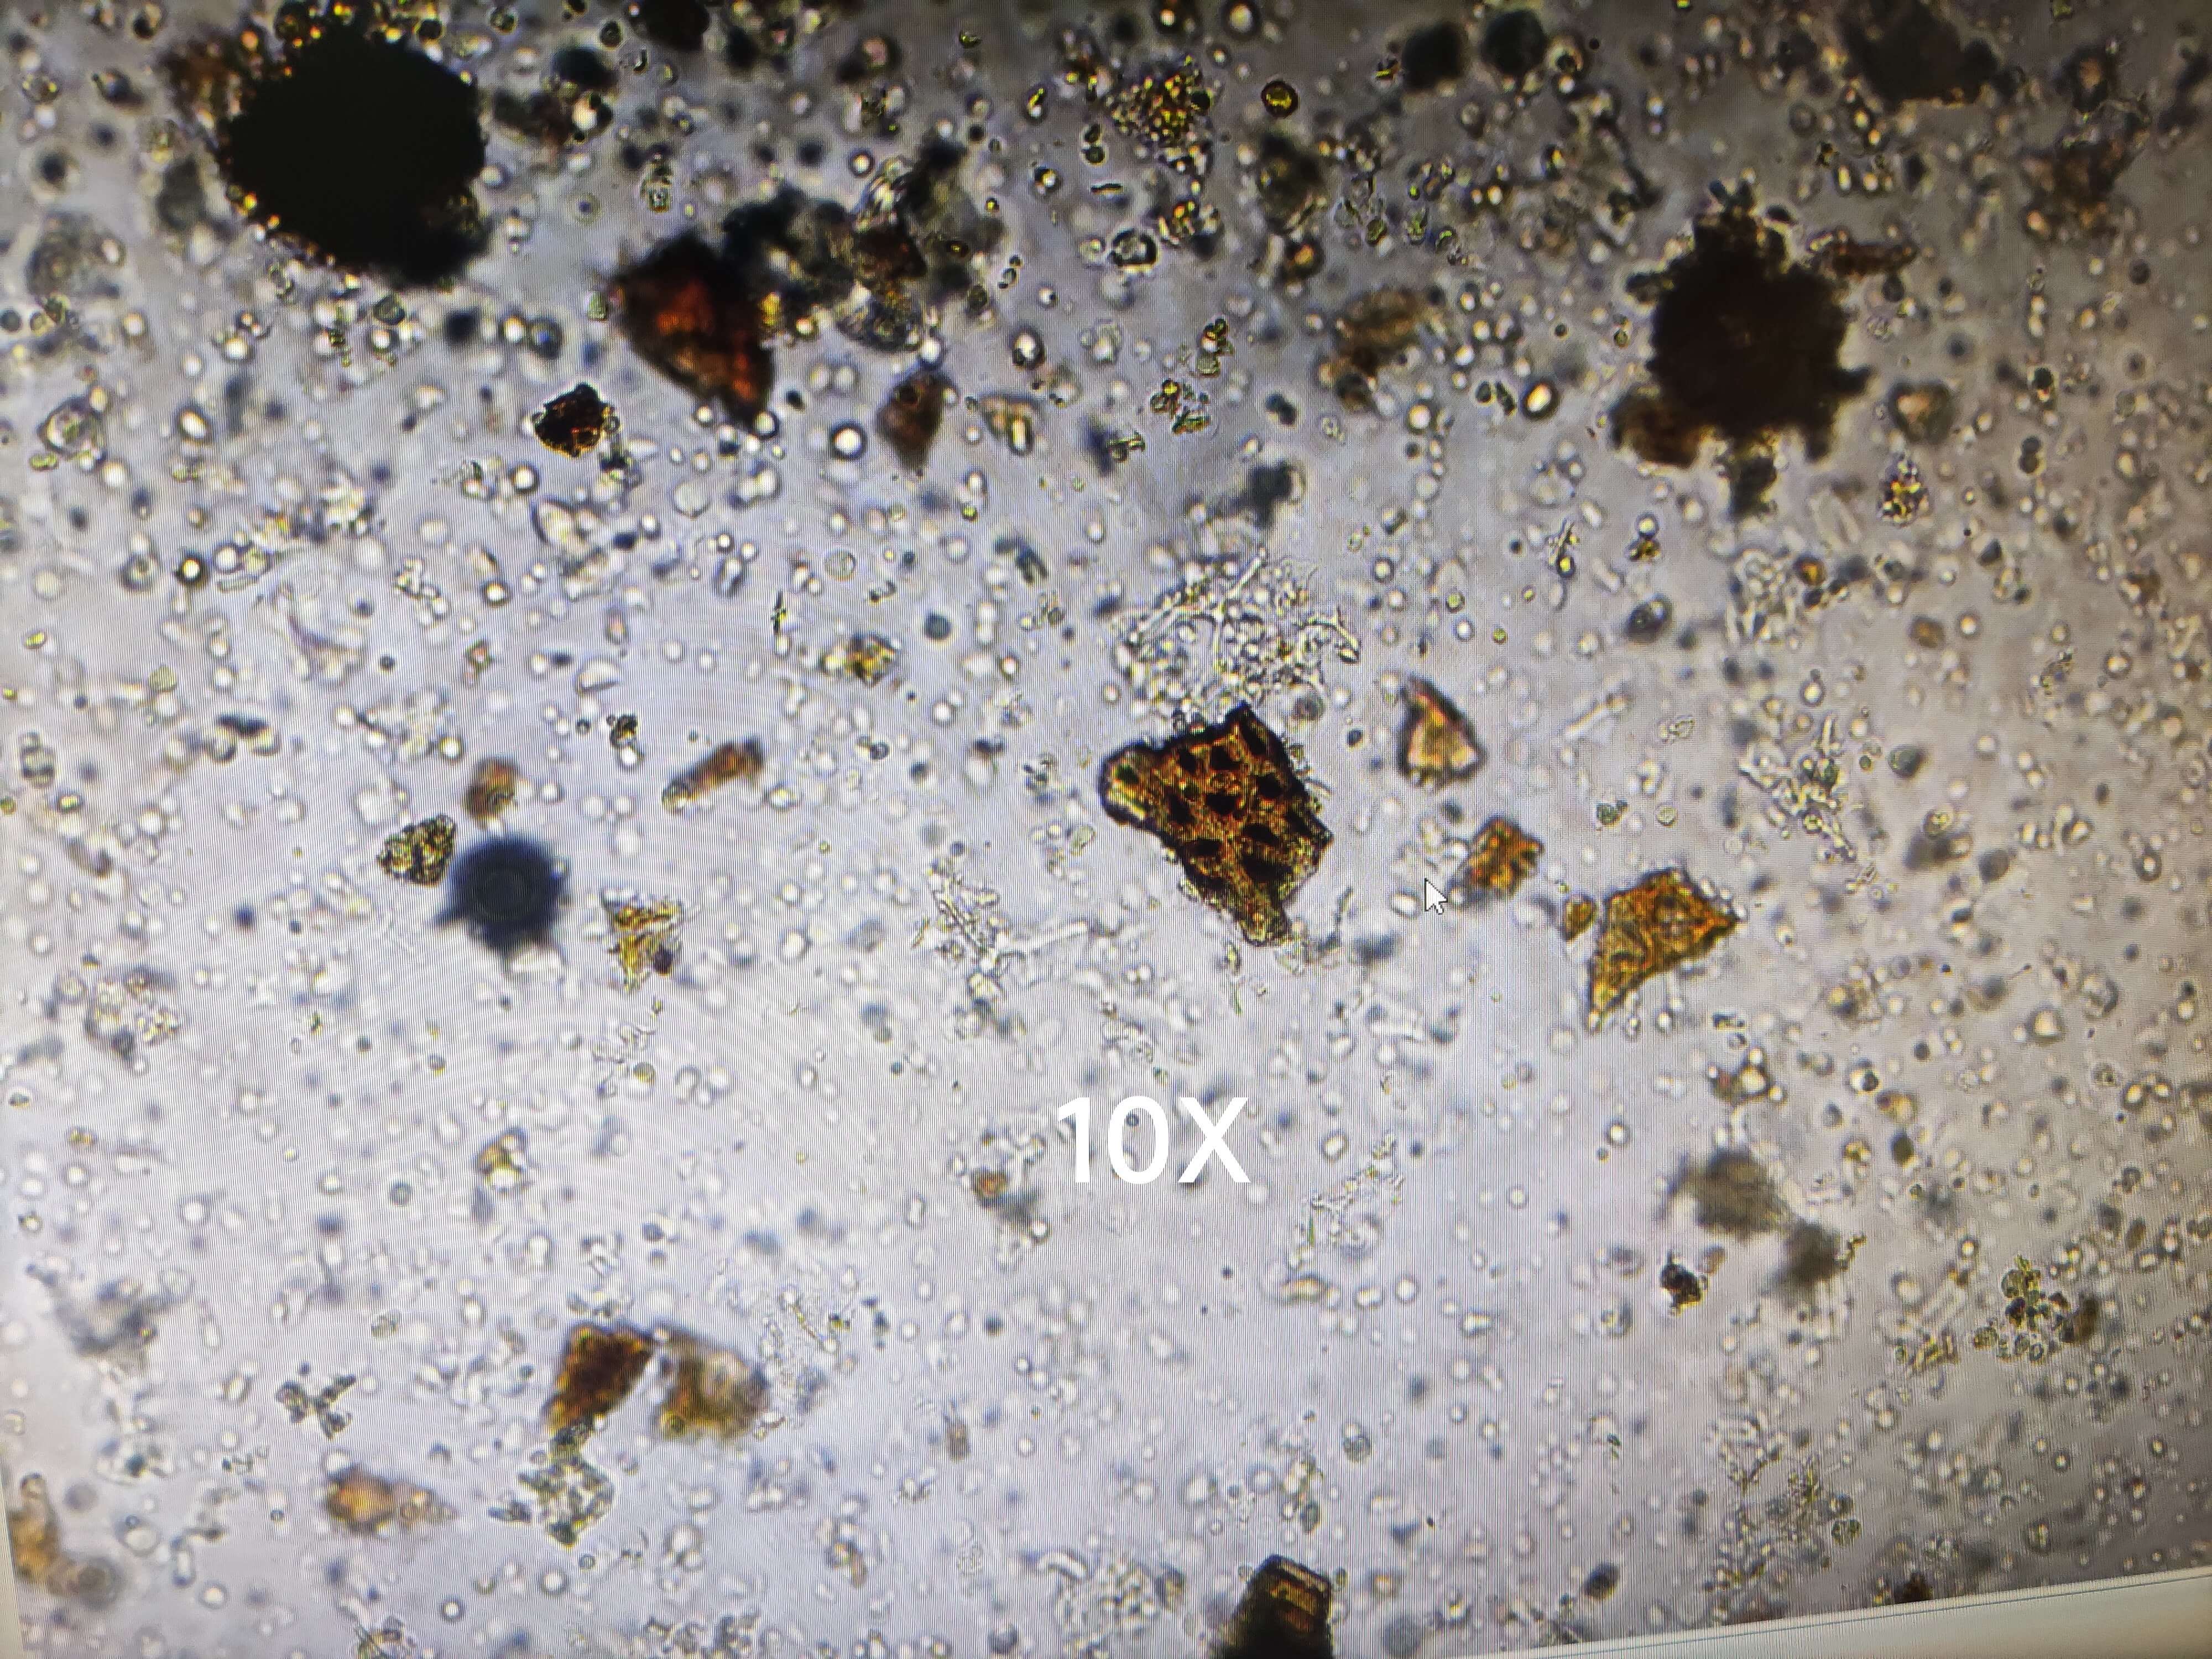

大黄

| 大黄 |

|---|

| 【参考标准】《中国药典》2020年版一部 |

| 【显微鉴别】 粉末黄棕色。草酸钙簇晶直径20~160μm,有的至 190μm。具缘纹孔导管、网纹导管、螺纹导管及环纹导管非木化。淀粉粒甚多,单粒类球形或多角形,直径3~45μm,脐点星状;复粒由2~8分粒组成。 |

| 【显微重点】 草酸钙簇晶甚大,且数量较多。 |

| 【图谱来源】 《中药成方制剂显微图典》 |